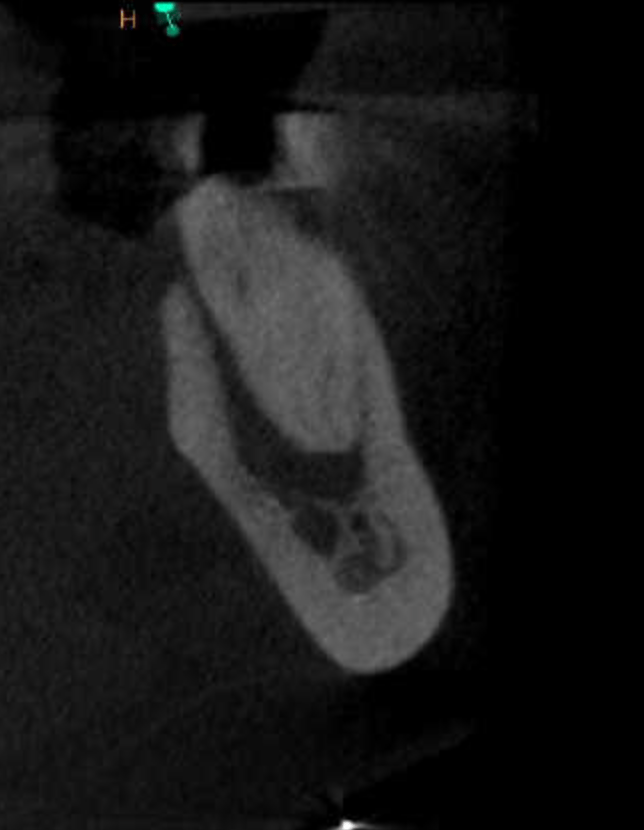

Premolar calcificado lesion